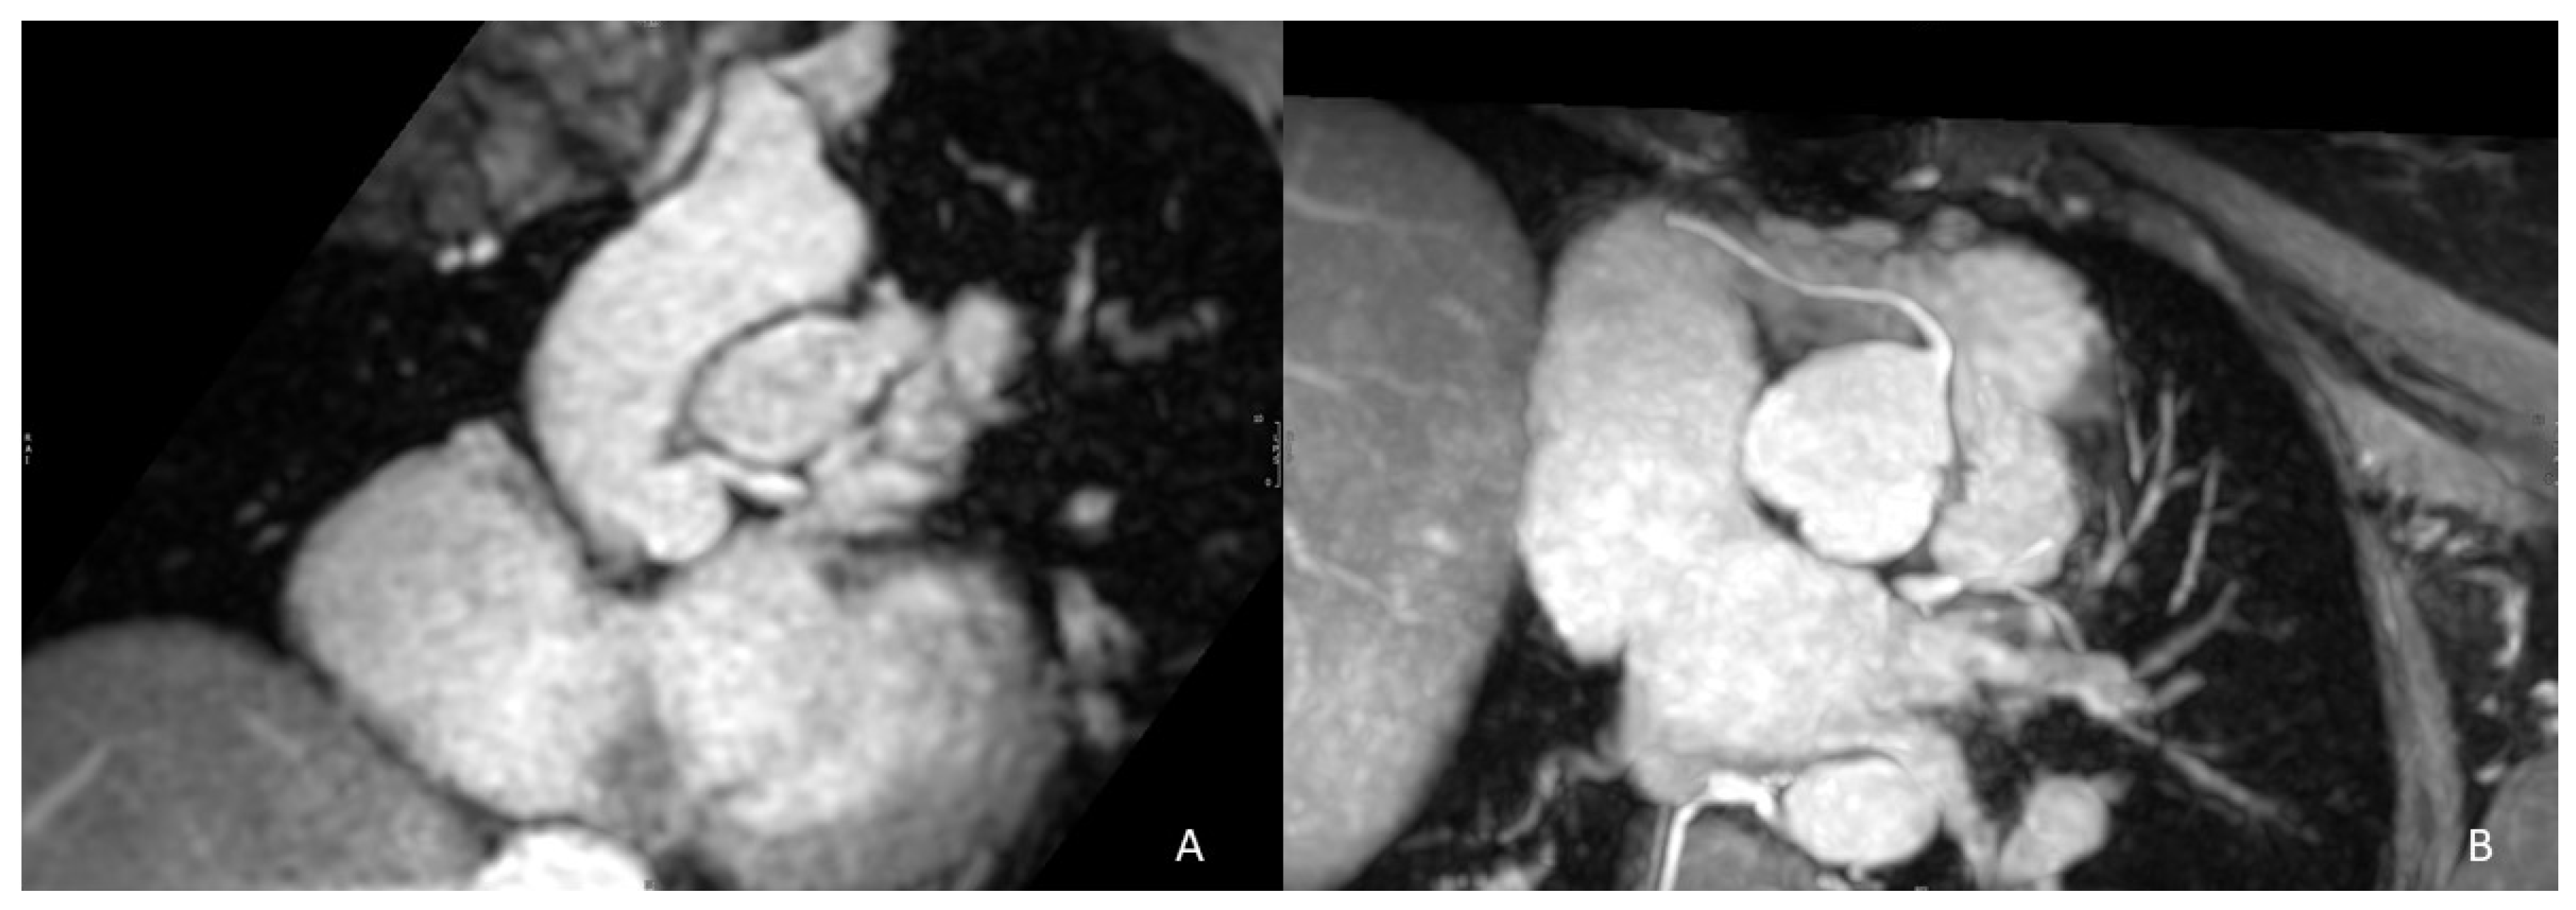

| 3D whole-heart | Comprehensive view of thoracic and cardiac anatomy | PROs - Free-breathing - No contrast-medium - Coronary imaging - ECG triggering: RVOT measurements at end-systole or end-diastole (static sequences) CONs - Long acquisition times - High susceptibility to metal artefacts |

| ceMRA | Right cardiac chambers RVOT PA | PROs - Single breath-hold - Fast acquisition times CONs - Contrast medium - No coronary imaging - No ECG triggering (blurring artefacts) |